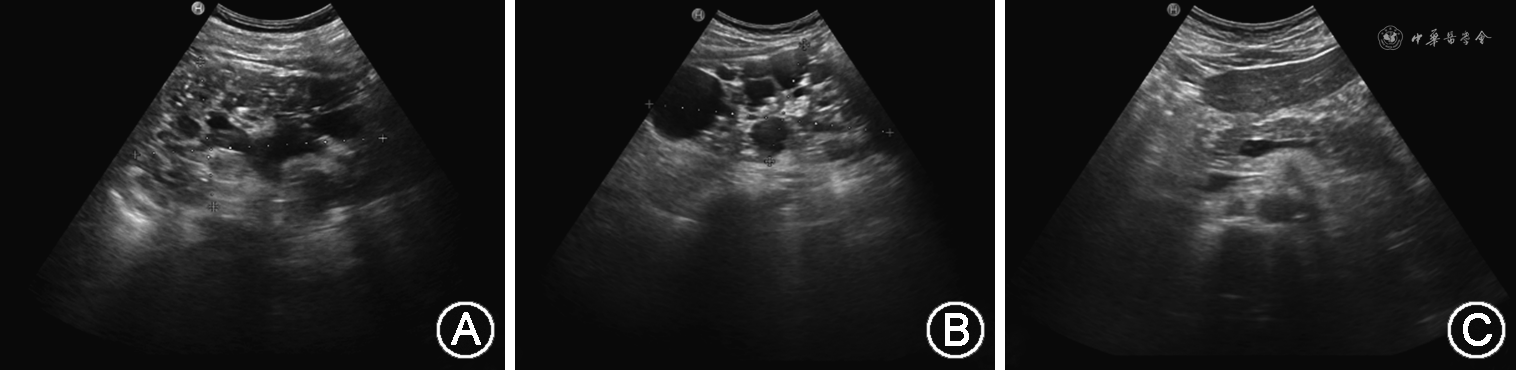

1. 先证者临床表型:先证者入院血压:170/103 mmHg(1 mmHg=0.133 kPa);24 h动态血压结果提示:(1)24 h血压平均值:139/86 mmHg;(2)白天血压均值:141/85 mmHg;(3)夜间血压平均值:135/87 mmHg;(4)夜间血压下降率:2.4%~4.3%,24 h血压呈非勺型。尿常规检测潜血阳性,血肌酐升高。B超示:双肾体积增大并异常回声,考虑成人型多囊肾并多发结石;肝囊肿。主要表现为:双肾体积增大,大小分别约130 mm×76 mm(左)、144 mm×72 mm(右);肾内充满众多大小不一的无回声区,较大分别约33 mm×22 mm(左)、48 mm×44 mm(右),囊与囊之间见少量肾实质回声;集合系统受压变形,肾盂、肾盏内见多个点状、斑状或团状强回声,左肾集合系统分离约17 mm,见图2A、B。肝脏实质回声欠均匀,肝内见数个无回声区,较大约15 mm×11 mm,边界清,内透声好,见图2C。中腹部CT示:双侧多囊肾改变伴左肾结石,肝脏多发囊肿。